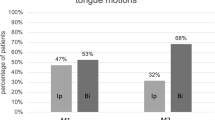

Delineation of HGN selective stimulation area

Starting from the hyoid bone, selective nervous branches for GGh and GGo were localized at 44 ± 8 and 59 ± 8%, respectively, of the geniohyoid distance with a mean common central point for both branches located at 52 ± 8% on the anteroposterior axis and 5.8 ± 1.1 mm from the inferior border of the GG muscle. The stimulation surface was represented by an ellipse of 4.4 ± 1.1 mm short axis (height) and 6.9 ± 3.8 mm long axis (length), with an absolute area of 23.8 ± 3.3 mm2 (Fig. 4).

Delineation of HGN selective stimulation area. Starting from the hyoid bone, selective nervous branches for GGh and GGo were, respectively, localized at 44 ± 8 and 59 ± 8% of the geniohyoid distance, with a mean common central point (black cross) for both branches located roughly at the midpoint of anteroposterior axis (52 ± 8%) and 5.8 ± 1.1 mm from the inferior border of the GG muscle. The area of stimulation (dotted line) was represented by an ellipse of 4.4 ± 1.1 short axis and 6.9 ± 3.8 mm long axis, with an absolute surface (red shadow area) of 23.8 ± 3.3 mm2 (color figure online)